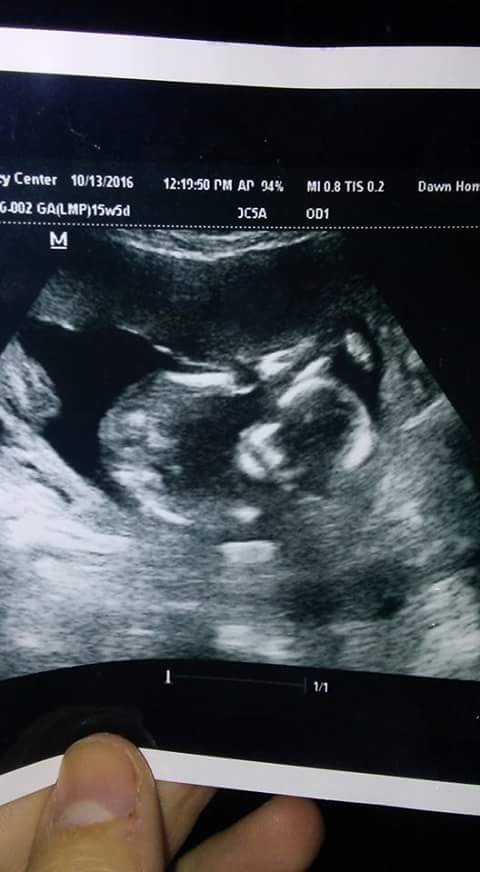

Here's our baby at 15 weeks! Knees touching the forehead, hahaha. The tech looked between the legs and there wasn't much there so I am still team pink! Hoping to find out more definitively soon!